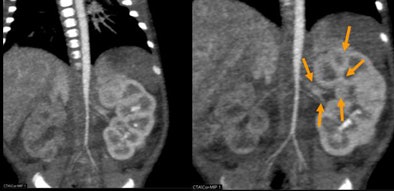

| Newborn with aortic hypoplasia and renal artery stenosis. Weight of 1.7 kg; single-rotation 320-detector-row scan at 0.5 sec, 80 kV, 40 mA, and dose of 0.3 mSv. All images courtesy of Dr. Patrik Rogalla. |